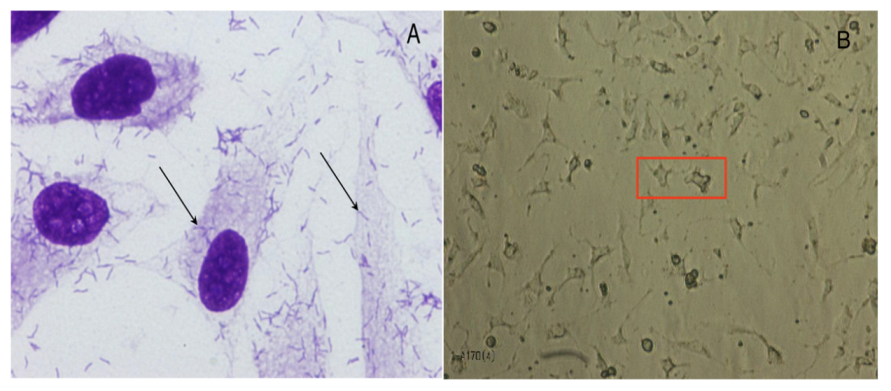

4.3.2. Bacterial Adherence and Toxicity